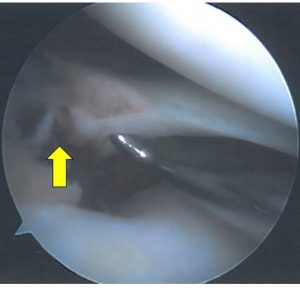

Όμως σε εντοπισμένες και διαγνωσμένες ρήξεις μηνίσκου με παρεκτόπηση συνήθως η συντηρητική θεραπεία αποτυγχάνει και οι πλείστες αντιμετωπίζονται με αρθροσκοπική θεραπεία.

Η αρθροσκοπική θεραπεία έσω και έξω μηνίσκου είναι μια μοντέρνα μέθοδος όπου με δύο ή τρείς μικρές οπές στο έσω και έξω μεσάρθριο διάστημα με τη βοήθεια αρθροσκοπίου και εξειδικευμένων εργαλείων γίνεται αντιμετώπιση και θεραπεία της ρήξης του έσω και έξω μηνίσκου.

Σε περιφερικές ρήξεις που υπάρχει σχετική αιμάτωση και αγγείωση στον μηνίσκο κυρίως σε νέα άτομα κάτω των 35-40 ετών γίνεται προσπάθεια συρραφής του μηνίσκου.